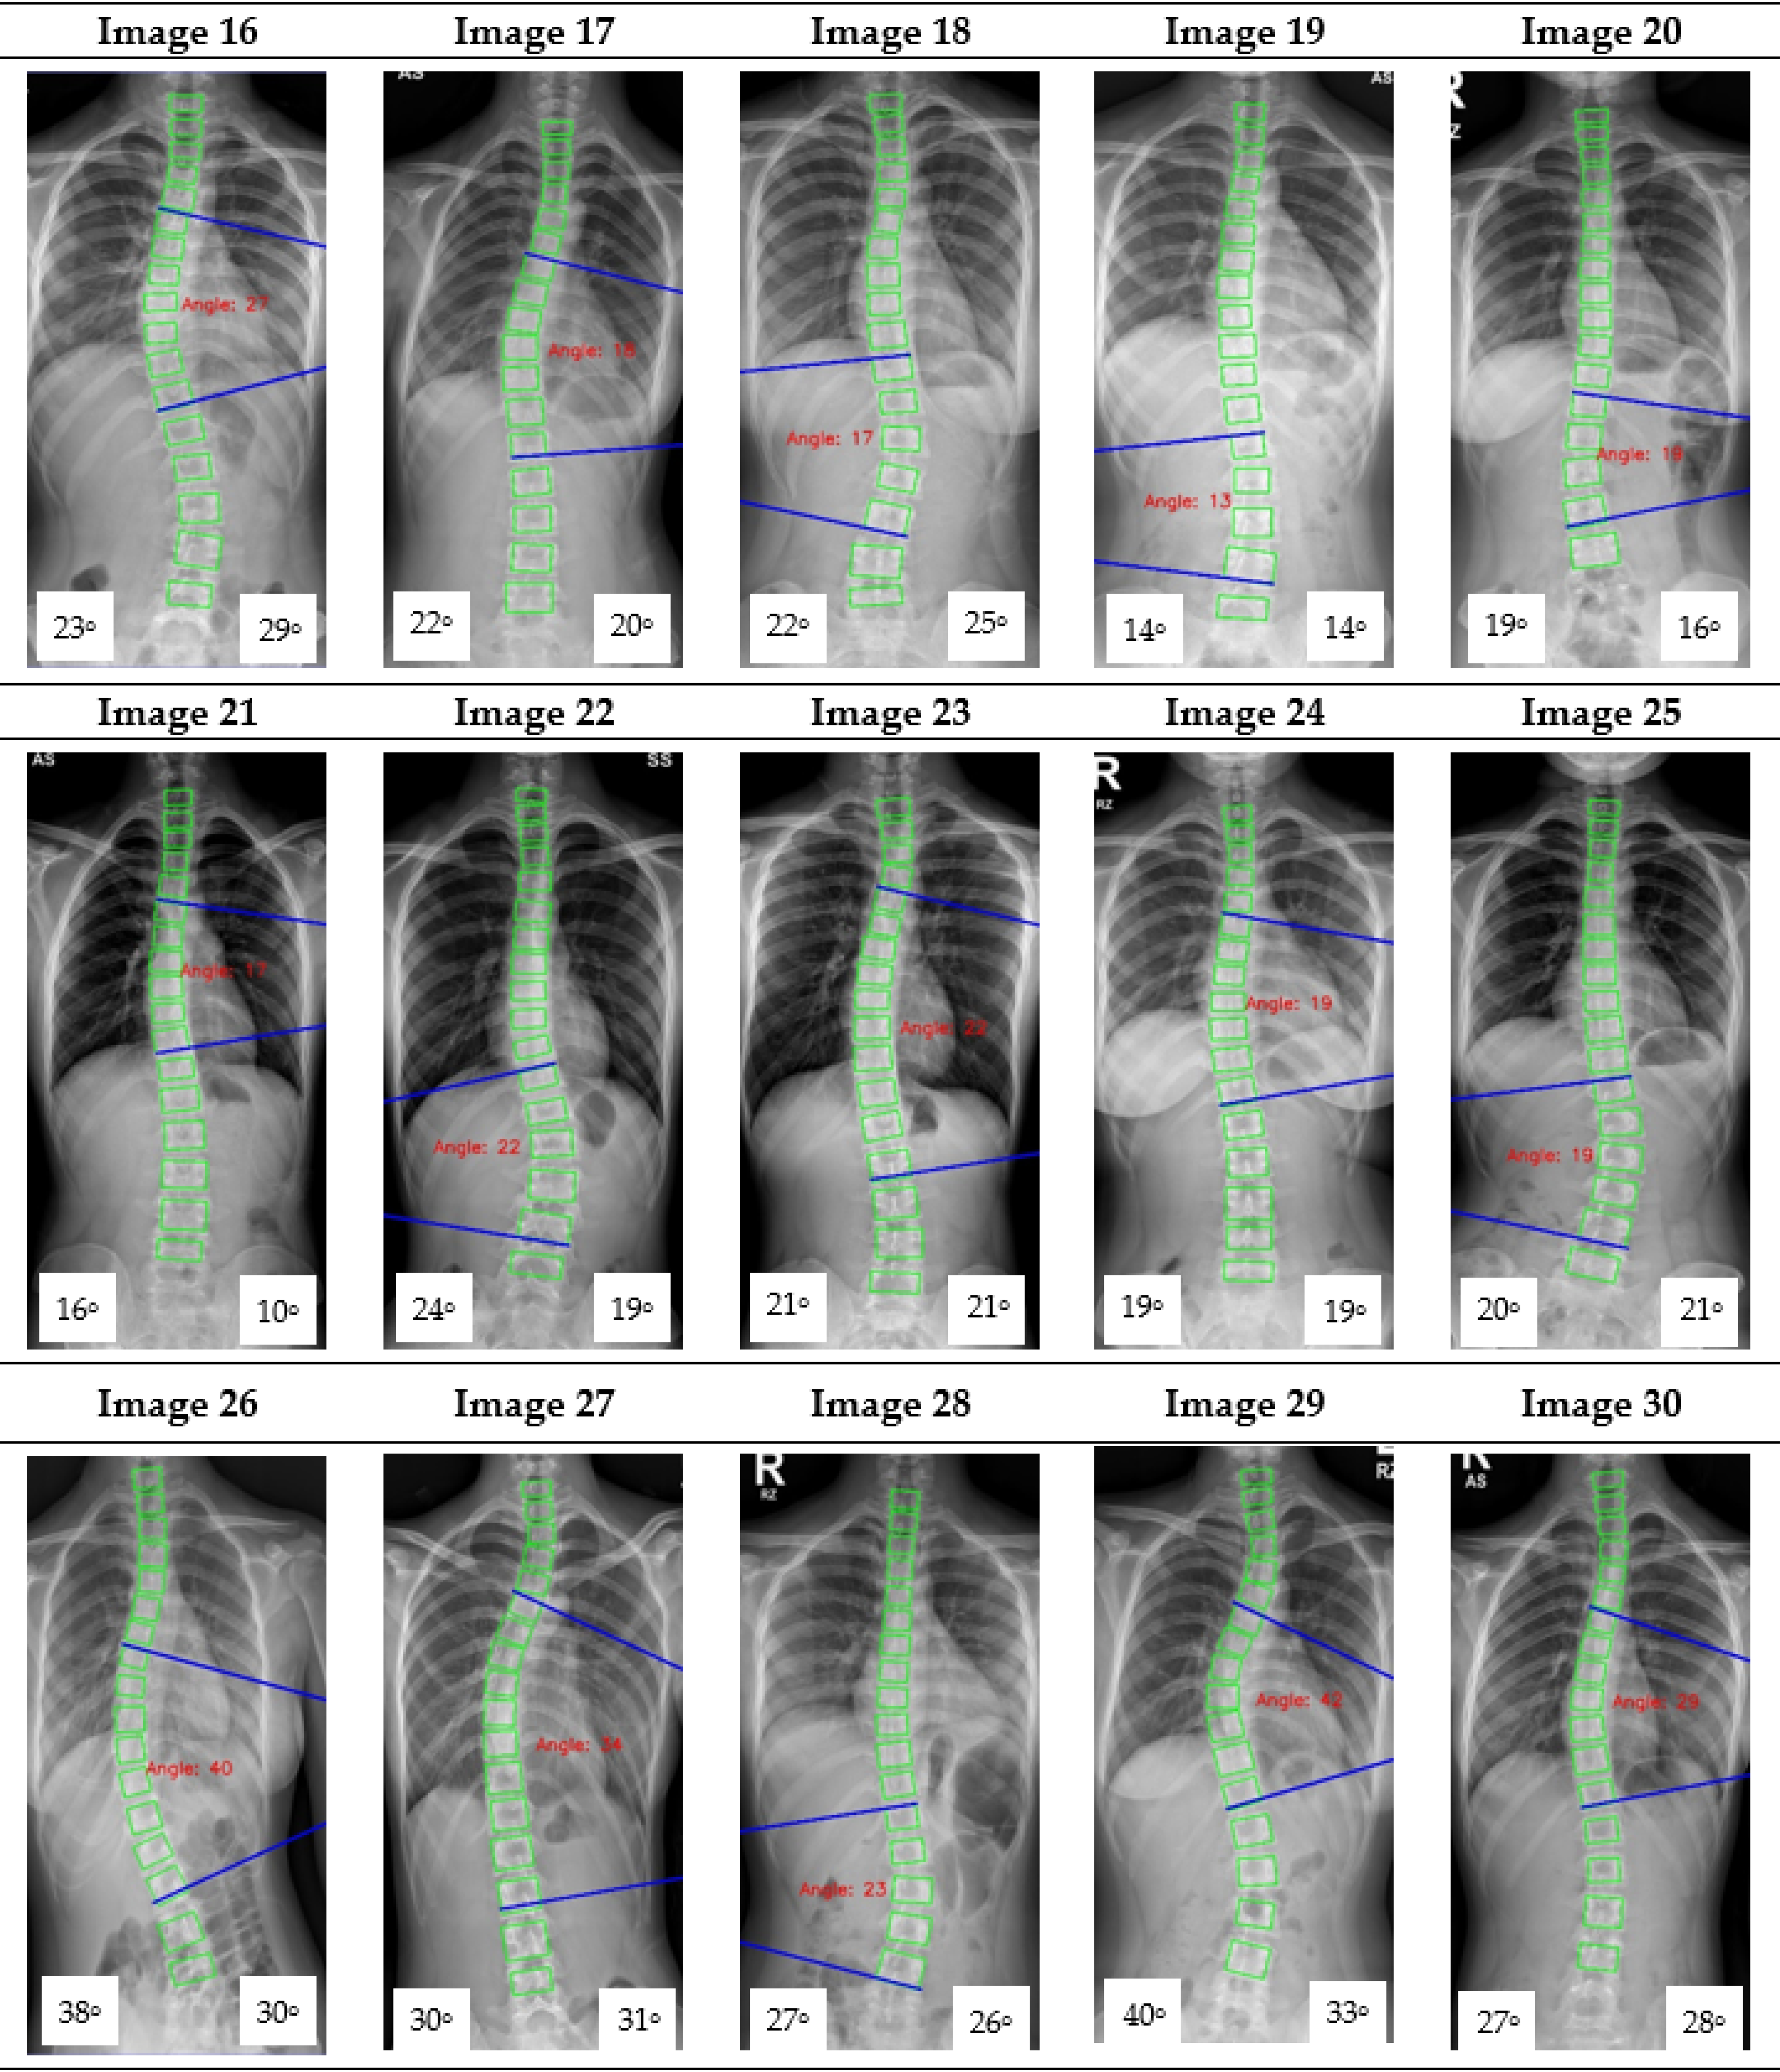

Figure A1.

The red font inside the X-ray image is a CNN CA measurement. Observer 1 and 2 evaluation is presented on the bottom left and right, respectively.